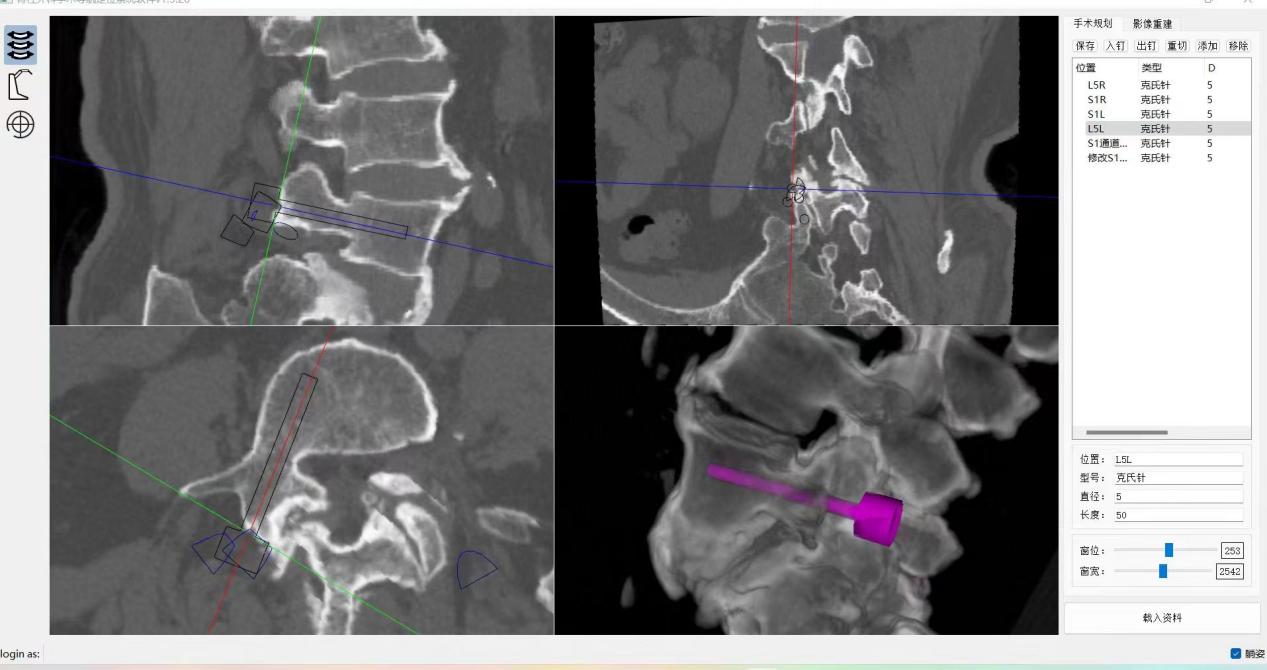

ORTHBOT脊柱机器人术前设计及术中穿刺

,均建议采取传统外科开放手术治疗,患者因担心手术风险,迟迟不愿手术。经多方打听,患者慕名找到李全义主任医师。入院后李全义主任医师仔细研究患者的疾病特点,经过充分的沟通,决定采用目前骨科先进的微创、精准技术—机器人辅助微创手术。李全义主任医师团队顺利为患者实施ORTHBOT脊柱机器人辅助镜下腰5椎体滑脱复位椎管减压椎间融合内固定术,以机器人辅助微创手术解决了患者的痛苦,减少手术创伤及并发症,缩短手术时间。手术利用术前患者的影像学资料,模拟建立穿刺路径及各项参数,极大地优化手术方案使其更加精准、安全、有效,显著降低了制钉过程中神经根损伤的风险。